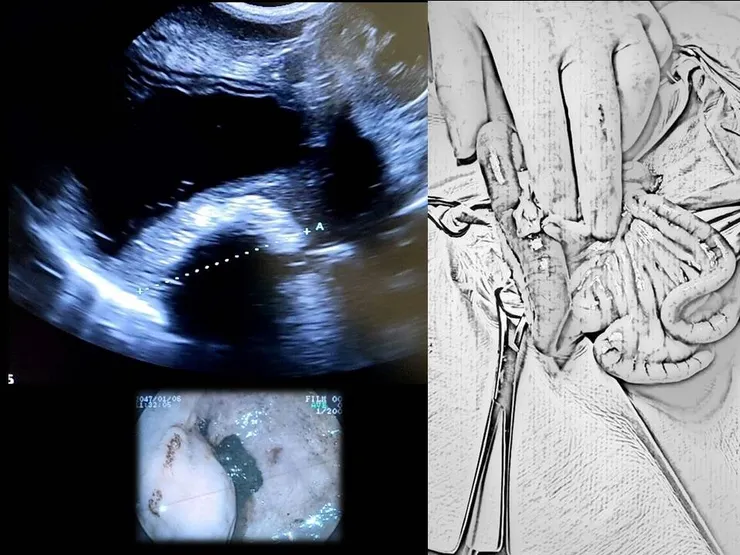

這些狀況也可以是各種疾病引起,因此在檢查上除了影像學(X光、超音波)的檢查之外,血液檢查也能幫助我們排除其他的疾病。

已經確認是完全腸阻塞或已經進展到腸穿孔時,立即進行手術會是第一優先;而下消化道的部分阻塞,也會在在診斷後12小時內進行手術。部分的動物可能會需要花些時間來校正體液、酸鹼值和電解質。大多數動物都可以在經過短時間部分矯正後能有足夠的身體狀況來進行手術。

手術過程中除了移除已經知道的阻塞部位外,獸醫師們大多會再仔細的巡過一次全部的腸道確保不會有其餘的異物仍存在於消化道之中。而腸道的健康狀況則會依據腸道的顏色、動脈的搏動狀況、腸道蠕動和傷口切割後的出血表現等等主觀的因素來評估是否健康或是需要進行截腸手術。